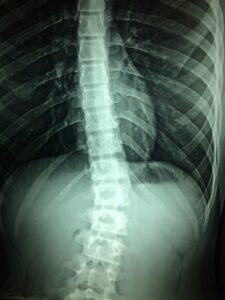

The first time, I was flat on my back in pain for three months, unable to walk, stand, or sit for more than 1 1/2 minutes at a time without excruciating pain. The orthopedic surgeon pointed to the MRI images and said that I had a “massive herniated disc and sciatica”.

In the second situation, I had severe neuropathy in my lower leg – completely different from sciatica. (I know all too well the signs and symptoms of sciatica.) This time, the MRIs did Not reveal a smoking gun – there was NO clear pathology!